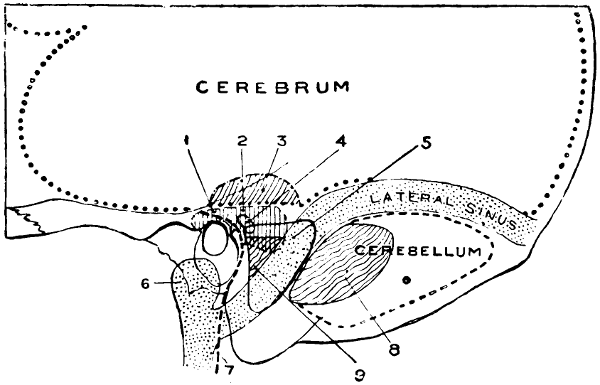

Fig. 1. Cranio-cerebral Topography. 1, The nasion; 2, The inion; 3, The mid-point between nasion and inion; 4, The Rolandic fissure; 5, The superior temporal crest; 6, The inferior temporal crest; 7, The Sylvian point; 8, The anterior horizontal limb of the Sylvian fissure; 9, The vertical limb of the Sylvian fissure; 10, The posterior horizontal limb of the Sylvian fissure; 11, The parietal prominence; 12, The malar tubercle; 13, The lambda; 14, The first temporo-sphenoidal sulcus; 15, The external parieto-occipital sulcus; 16, The lateral sinus; 17, 17, 17, The level of the base of the cerebrum; 18, The external auditory meatus; 19, 19, Reid’s base-line. (Reproduced, by the permission of Mr. H. K. Lewis, from the author’s work on ‘Landmarks and Surface-markings’.)

Fig. 2. Cranio-cerebral Topography. 1, 1, Reid’s base-line; 2, 2, A line parallel to the above at the level of the supra-orbital margin; 3, The middle meningeal artery; 4, The anterior branch; 5, 5, 5, The three sites for trephining; 6, The posterior branch; 7, The site for trephining; 8, The point for trephining to reach the descending horn of the lateral ventricle; 9, The lateral sinus; 10, The inion; 11, The mastoid process; 12, Macewen’s suprameatal triangle; 12a, The mastoid antrum; 12b, The facial nerve; 13, The suprameatal and supramastoid crests; 14, 14, The temporal crest; 15, The temporal fossa; 16, The external angular frontal process; 17, The tendo-oculi attachment; 18, The lachrymal groove. (Reproduced, by the permission of Mr. H. K. Lewis, from the author’s work on ‘Landmarks and Surface-markings’.)